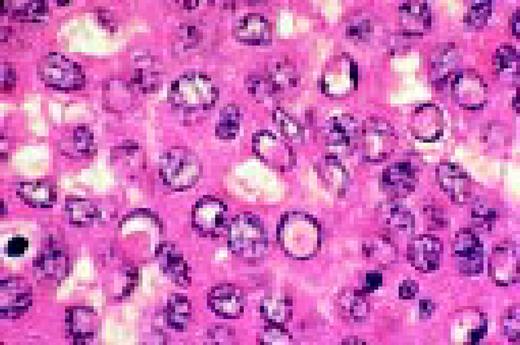

Slide L39

Multiple myeloma, bone marrow aspirate. Virtually every cell in the field is a neoplastic plasma cell. They show nuclear eccentricity, pleomorphism, and a tendency to stick together in clumps.FIG39